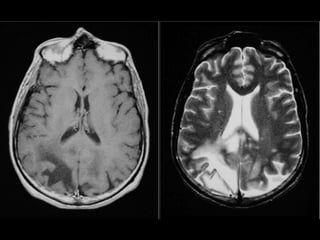

critérios  McDonald  (2017)   • disseminação  no  espaço   – RM  por  ≥  1  lesões  hiperintensas  em  T2,   sintomá+cas  ou  assintomá+cas,  que  são   caracterís+cos  de  EM,  em  dois  ou  mais  das   seguintes  quatro  áreas  do  sistema  nervoso   central:     • periventricular,     • cor+cal/justacor+cal,  infratentorial  e  medula  espinhal.

• disseminação  no  tempo   – presença  simultânea  de  lesões  captantes  de   gadolíneo  e  lesões  não  captantes  em  qualquer   exame  de  RM,     – ou  nova  lesão  hiperintensa  em  T2  ou  captante  de   gadolínio  quanto  comparada  a  um  exame  de  RM   prévio,  independentemente  do  momento  em  que   foi  realizado.

Diagnóstico:   Observação: ARM pode evidenciar áreas com pontos brilhantes indefinidos em indivíduos saudáveis; Gadolínio: • realçar lesões, • destacar se a doença está em estado ativo